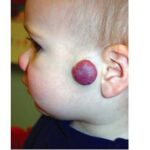

Most cases are acquired early in childhood and have a protracted course. Rare congenital forms also exist. TAs display various clinical patterns. They may present as a subtle stain-like area that later thickens, as a large, plaque-like, infiltrated, red or dusky blue-purple lesion, or as an exophytic, firm, violaceous, cutaneous nodule (Fig. 126-11). TA must be differentiated from infantile hemangiomas as well as other vascular tumors. They are often somewhat firmer and may be tender. Histologically, both acquired and congenital TAs demonstrate vascular tufts of tightly packed capillaries, randomly dispersed throughout the dermis in a typical “cannonball distribution” with crescentic spaces surrounding the vascular tufts, and lymphatic-like spaces within the tumor stroma.